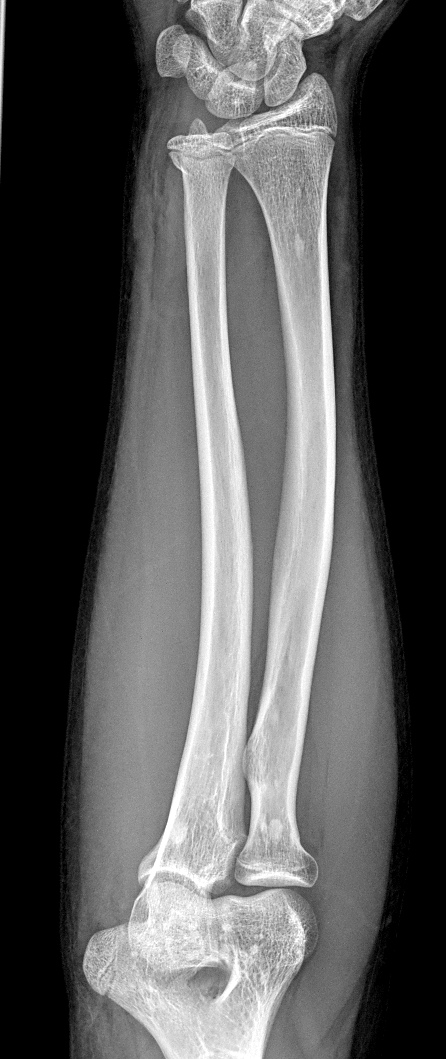

Info Images Findings Impression Reco/Acuity Case Images View Images / Launch Visage Case Notes History 2-month-old presents with decreased right arm movement, increased fussiness, and increased sleepiness for 2 days. Suspected non-accidental trauma. Exam Skeletal survey Prior Study none Dicom View Reference Material

Section 1 Submit Findings CB1550 Findings Skeletal Survey - Technique Check Skull AP/Lat Yes No Cervical and Thoracolumbar spine Yes No Chest X-Ray Yes No Ribs – Left/Right Oblique Yes No Abdominal X-Ray Yes No Pelvis with both hips Yes No Bilateral Humerus, Forearm, Hand Yes No Bilateral Femur, Tibia/fibula, feet Yes No Any additional lateral views of the extremities Yes No The exam is over or under penetrated. Yes No The exam may or may not be limited by overlying structures or soft tissues, body habitus, patient positioning, support devices, or motion. Yes No The area of concern is indicated by the patient, technologist, or care provider. Yes No The area of concern is included on the exam. Yes No Soft Tissues There is soft tissue swelling, indistinctness of fat/muscle planes, gas, or laceration in the area of clinical concern. Yes No There is an effusion, fat pad displacement, or fat fluid level. Yes No There is a radiodense or lucent foreign body. Yes No There are other densities, calcifications, post-surgical changes, or support devices in the soft tissues. Yes No Any support lines/tubes. Yes No Bone There is a break or interruption of the continuity of the cortical or cancellous bone. Yes No There is overriding of the trabeculae with apparent sclerosis. Yes No There is displacement of a fracture fragment. Yes No There is bowing of the bone in addition to the fracture at the apex of the bowed bone concerning for the greenstick. Yes No There is a spiral fracture of the leg concerning for toddler’s fracture. Yes No There is abnormal angulation or bulging of the cortical surface relative to the normal cortex which could be from a buckle or torus fracture. Yes No There is a displaced fragment which may be from avulsion by a tendon, ligament, or joint capsule or from a comminuted or other fracture. Yes No The stress trabeculae or other trabeculae of the cancellous bone are interrupted or otherwise abnormal. Yes No There is subperiosteal or endosteal reaction which could indicate a healing or subacute fracture or other abnormality. Yes No There is hard/soft callus formation. Yes No There is remodeling of the bone. Yes No There is a corner fracture or metaphyseal lesion that could be from nonaccidental trauma. Yes No There are multiple fractures of different ages. Yes No There are vertebral body/spinous process fractures. Yes No There are rib fractures. Location - posterior or lateral. Yes No There is scapular/sternal fracture. Yes No There are fractures of the digits. Yes No There are wormian bones. Yes No There are intrasutural bones. Yes No There is metaphyseal abnormality (lucencies, increased density, erosion) which may be from something other than injury such as stress, metabolic disease (e.g. rickets with loss or distortion of the zone of the provisional calcification), neoplasm (e.g. leukemia), heavy metals, inflammation, or infection. Yes No There are metaphyseal spurs. Yes No There are bony deformities involving multiple bones. Yes No The bones are gracile. Yes No There are non-healing fractures. Yes No There is/are focal or multifocal lytic/lucent, blastic/sclerotic or mixed density lesion(s) or other abnormality. Yes No Overall bone density is increased or decreased with or without thinning or thickening of the cortical or cancellous bone. Yes No Growth plates, ossification centers, apophyses The growth plate(s) is/are abnormal. Yes No There is widening of the physis from a fracture with or without displacement of the epiphysis (Salter-Harris I). Yes No There is a fracture through the physis which then extends into the metaphysis with or without angulation or displacement (S-H II). Yes No There is a fracture through the physis which then extends into the epiphysis and is intra-articular, with or without angulation or displacement (S-H III). Yes No There is a fracture through the metaphysis, physis, and epiphysis which extends into the joint space with or without angulation or displacement (S-H IV). Yes No There is narrowing of the physis from a compression fracture (S-H V). Yes No The apophysis, epicondyle, secondary ossification center, or accessory ossicle is displaced or otherwise abnormal. Yes No The ossification centers are underdeveloped. Yes No Joints and alignment There is an effusion, fat pad displacement, or fat fluid level. Yes No The epiphysis or subchondral bone is fractured, interrupted, flattened, compressed, impacted, displaced, or otherwise abnormal. Yes No There is an intra-articular loose body or chondrocalcinosis. Yes No The joint is widened, narrowed, dislocated, malaligned, or incongruent. Yes No There is pseudoarthrosis. Yes No Other findings There are developmental changes or other anatomic variants or other existing conditions that may or may not be contributing to symptoms which can or should be further evaluated non-emergently or are otherwise incidental. Yes No The remainder of the exam is abnormal for age. Yes No The lungs show focal airspace opacity. Yes No There is pneumothorax. Yes No There is organomegaly. Yes No There is intra-abdominal calcification. Yes No There is displacement of the bowel loops. Yes No There is free intraperitoneal air. Yes No The bowel loops are dilated/obstructed. Yes No There is paraspinal soft tissue abnormality. Yes No